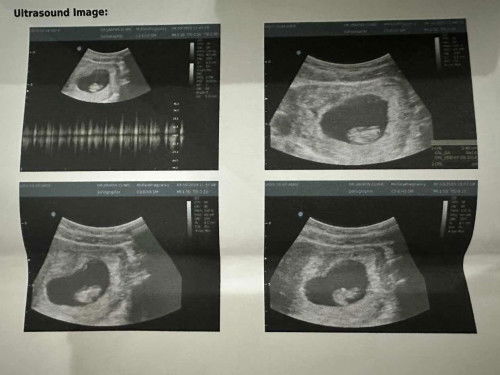

อัลตราซาวด์13วีค5dมีลูกบ้านไหนนอนคว่ำหน้าหัวทิ่มลงบ้างไหมค่ะ ปกติไหมคะ